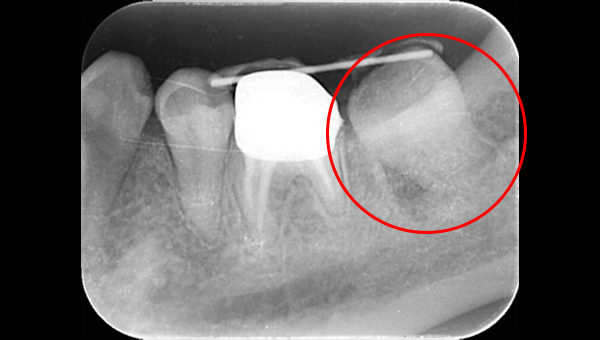

レントゲン写真

根管治療後3ヶ月です。根のまわりの骨がやや白くなってきているのがわかります。だんだん骨の添加がみられている証拠になります。

ここまで治癒していればかぶせ物をかぶせても問題ないと判断しました。